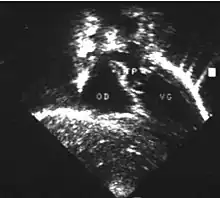

- Les coupes échographiques les plus utiles à cette fin sont :

- la coupe parasternale gauche grand axe : elle montre que le vaisseau issu du ventricule gauche (le plus postérieur) se dirige anormalement vers l'arrière et se bifurque précocement. C'est donc le tronc pulmonaire et non l'aorte comme normalement ;

- les coupes sous costales qui montrent bien le trajet parallèle des gros vaisseaux et leur inversion.